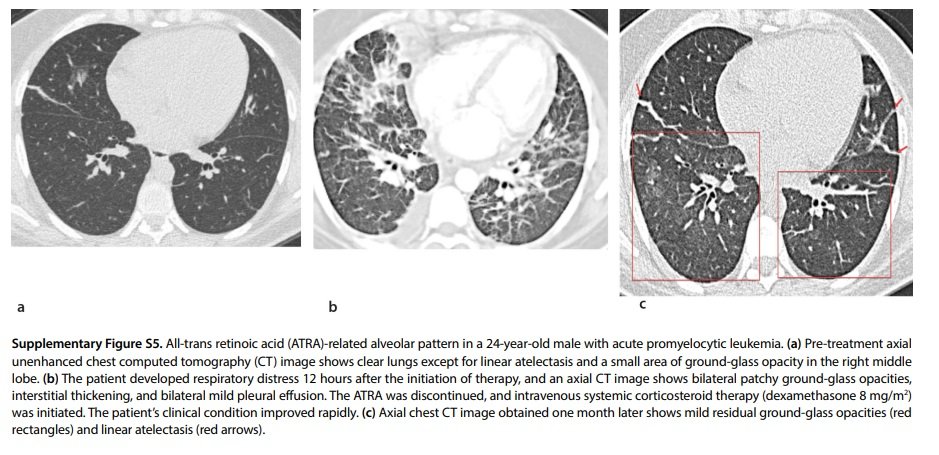

All-trans retinoic acid (ATRA)-related alveolar pattern in a 24-year-old male with acute promyelocytic leukemia.